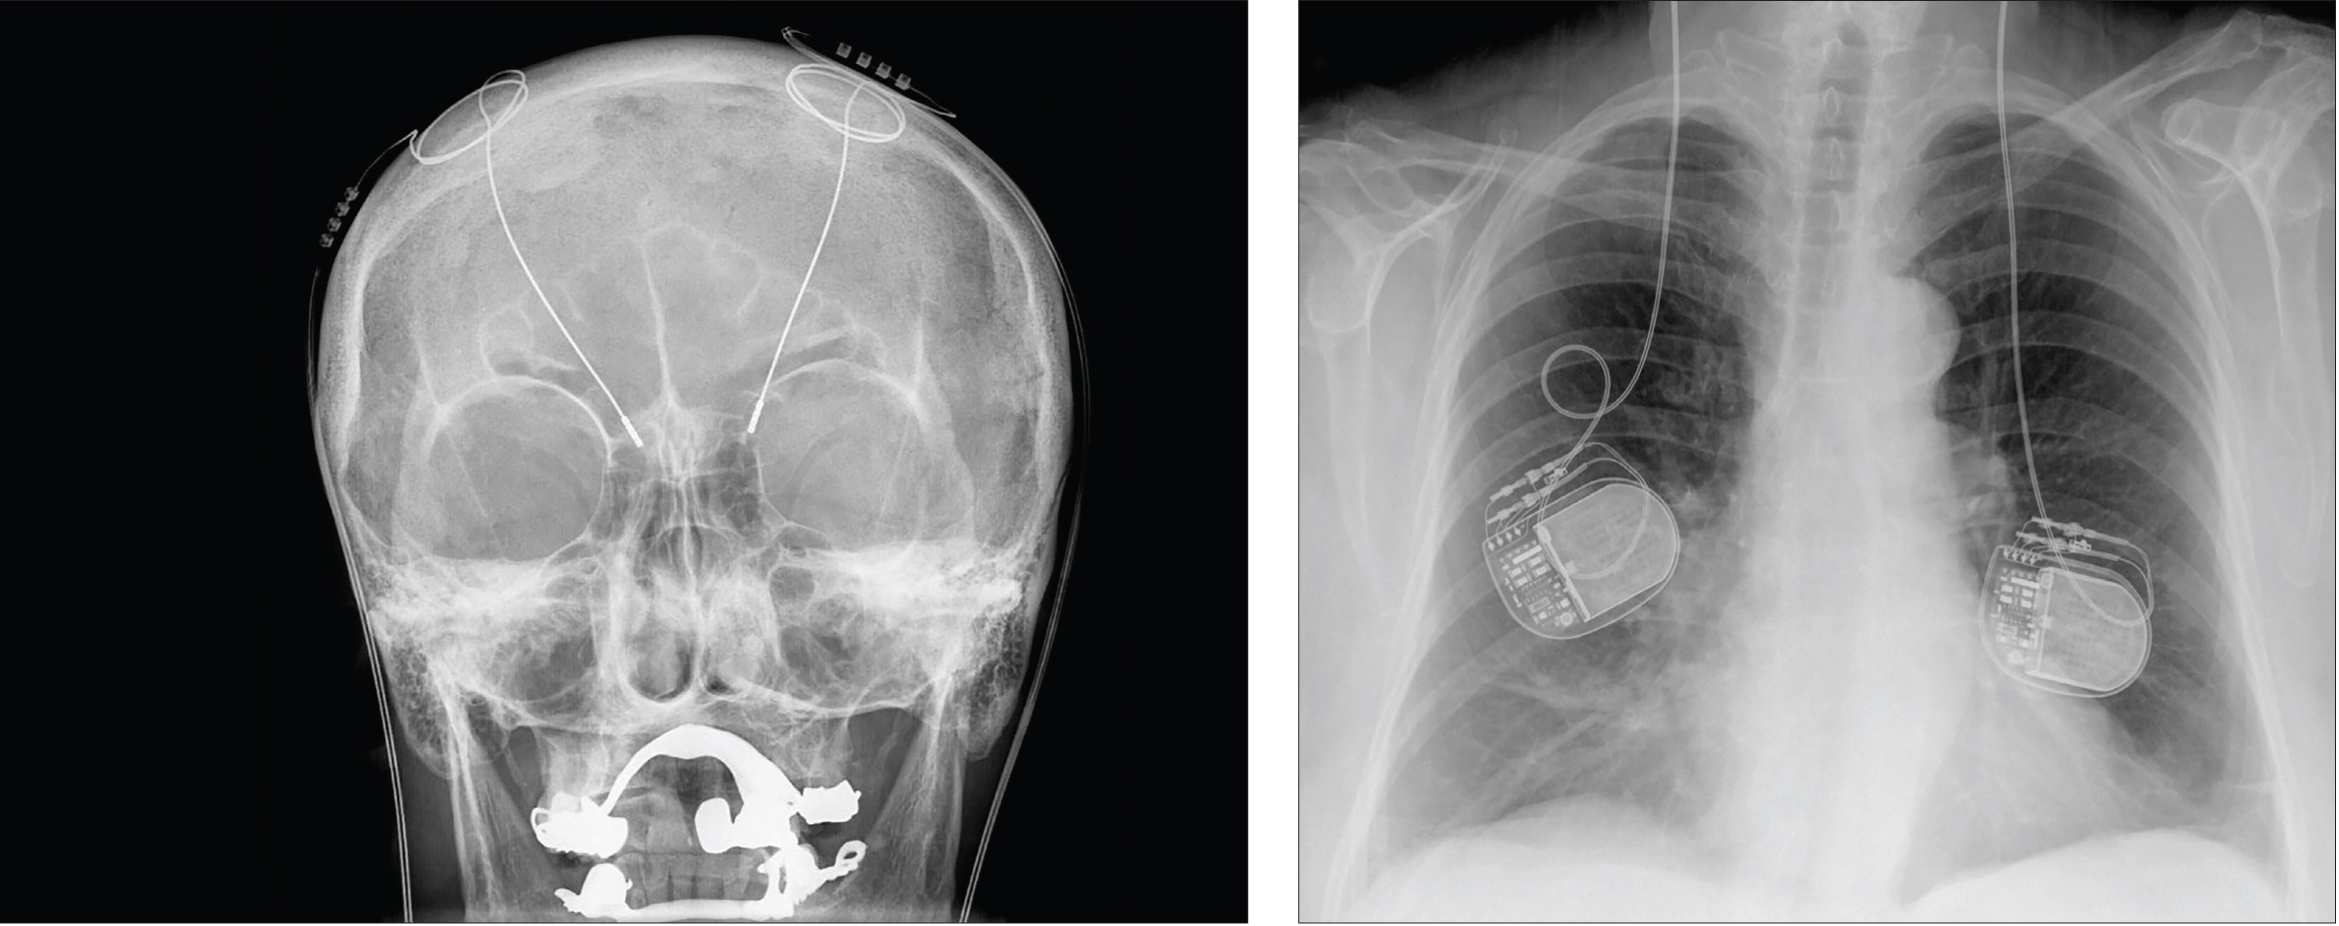

Insights into the pathophysiology of movement disorders have rekindled interest in the use of focused electrical stimulation as a form of treatment. The most advanced and precise method — deep brain stimulation (DBS) — was inspired by pacemakers engineered for the heart. Instead of electrodes implanted in the heart, the electrodes of the DBS device are surgically embedded in specific brain regions. Depending on where the electrodes are placed, DBS devices can help alleviate the symptoms of some brain disorders.

Insights into the pathophysiology of movement disorders have rekindled interest in the use of focused electrical stimulation as a form of treatment. The most advanced and precise method — deep brain stimulation (DBS) — was inspired by pacemakers engineered for the heart. Instead of electrodes implanted in the heart, the electrodes of the DBS device are surgically embedded in specific brain regions. Depending on where the electrodes are placed, DBS devices can help alleviate the symptoms of some brain disorders.

During most of these implantation surgeries, patients remain awake so that a neurologist can talk to them and ensure that the electrodes are stimulating the correct locations. While the patient’s head is held in place with a stereotactic frame, the surgeon drills a dime-sized hole (or smaller) in the skull. Then, a thin insulated wire with electrodes at the tip or along the shaft is inserted deep into the brain; if both sides of the brain are to receive implants, a wire is inserted into each side. In a separate surgery, a battery-operated pulse generator is implanted in the upper chest and connected to the electrodes. When the device is turned on, it starts sending electrical currents that alter the activity of the targeted brain cells.

The implanted device relies on the fact that neuronal communication uses electrical signals. In many movement disorders, an abnormal signal or pulse can gain control of a circuit and can easily become magnified. Like someone shouting in a crowded room, this aberrant signal can drown out other activity. DBS interrupts the shouting, so that normal communication can continue.

To determine where brain activity needs to be silenced or induced, neurosurgeons must identify the locations of the problems. The brain areas first targeted for tremors and Parkinson’s disease were chosen after years of painstaking neuroimaging, neuroanatomy, and fundamental research, especially in nonhuman primate models. Since then, deep brain stimulation has been used to treat epilepsy, dystonia, Tourette’s syndrome and, more recently, obsessive-compulsive disorder. Now researchers are investigating whether the DBS technique can potentially be extended to mood disorders such as treatment-resistant depression, as well as other complex mental disorders.

Hellerhoff.

Deep brain stimulation uses electrodes implanted deep in the brain, which carry electric impulses to specific brain regions. The power packs that provide the electricity are implanted in the patient’s back, as seen in this X-ray.

Yet DBS, like any surgical procedure, is not without some risks. It is highly invasive, and potential complications include infection, stroke, and bleeding in the brain. It also requires regular neurological follow-up and battery changes every 3 to 4 years.